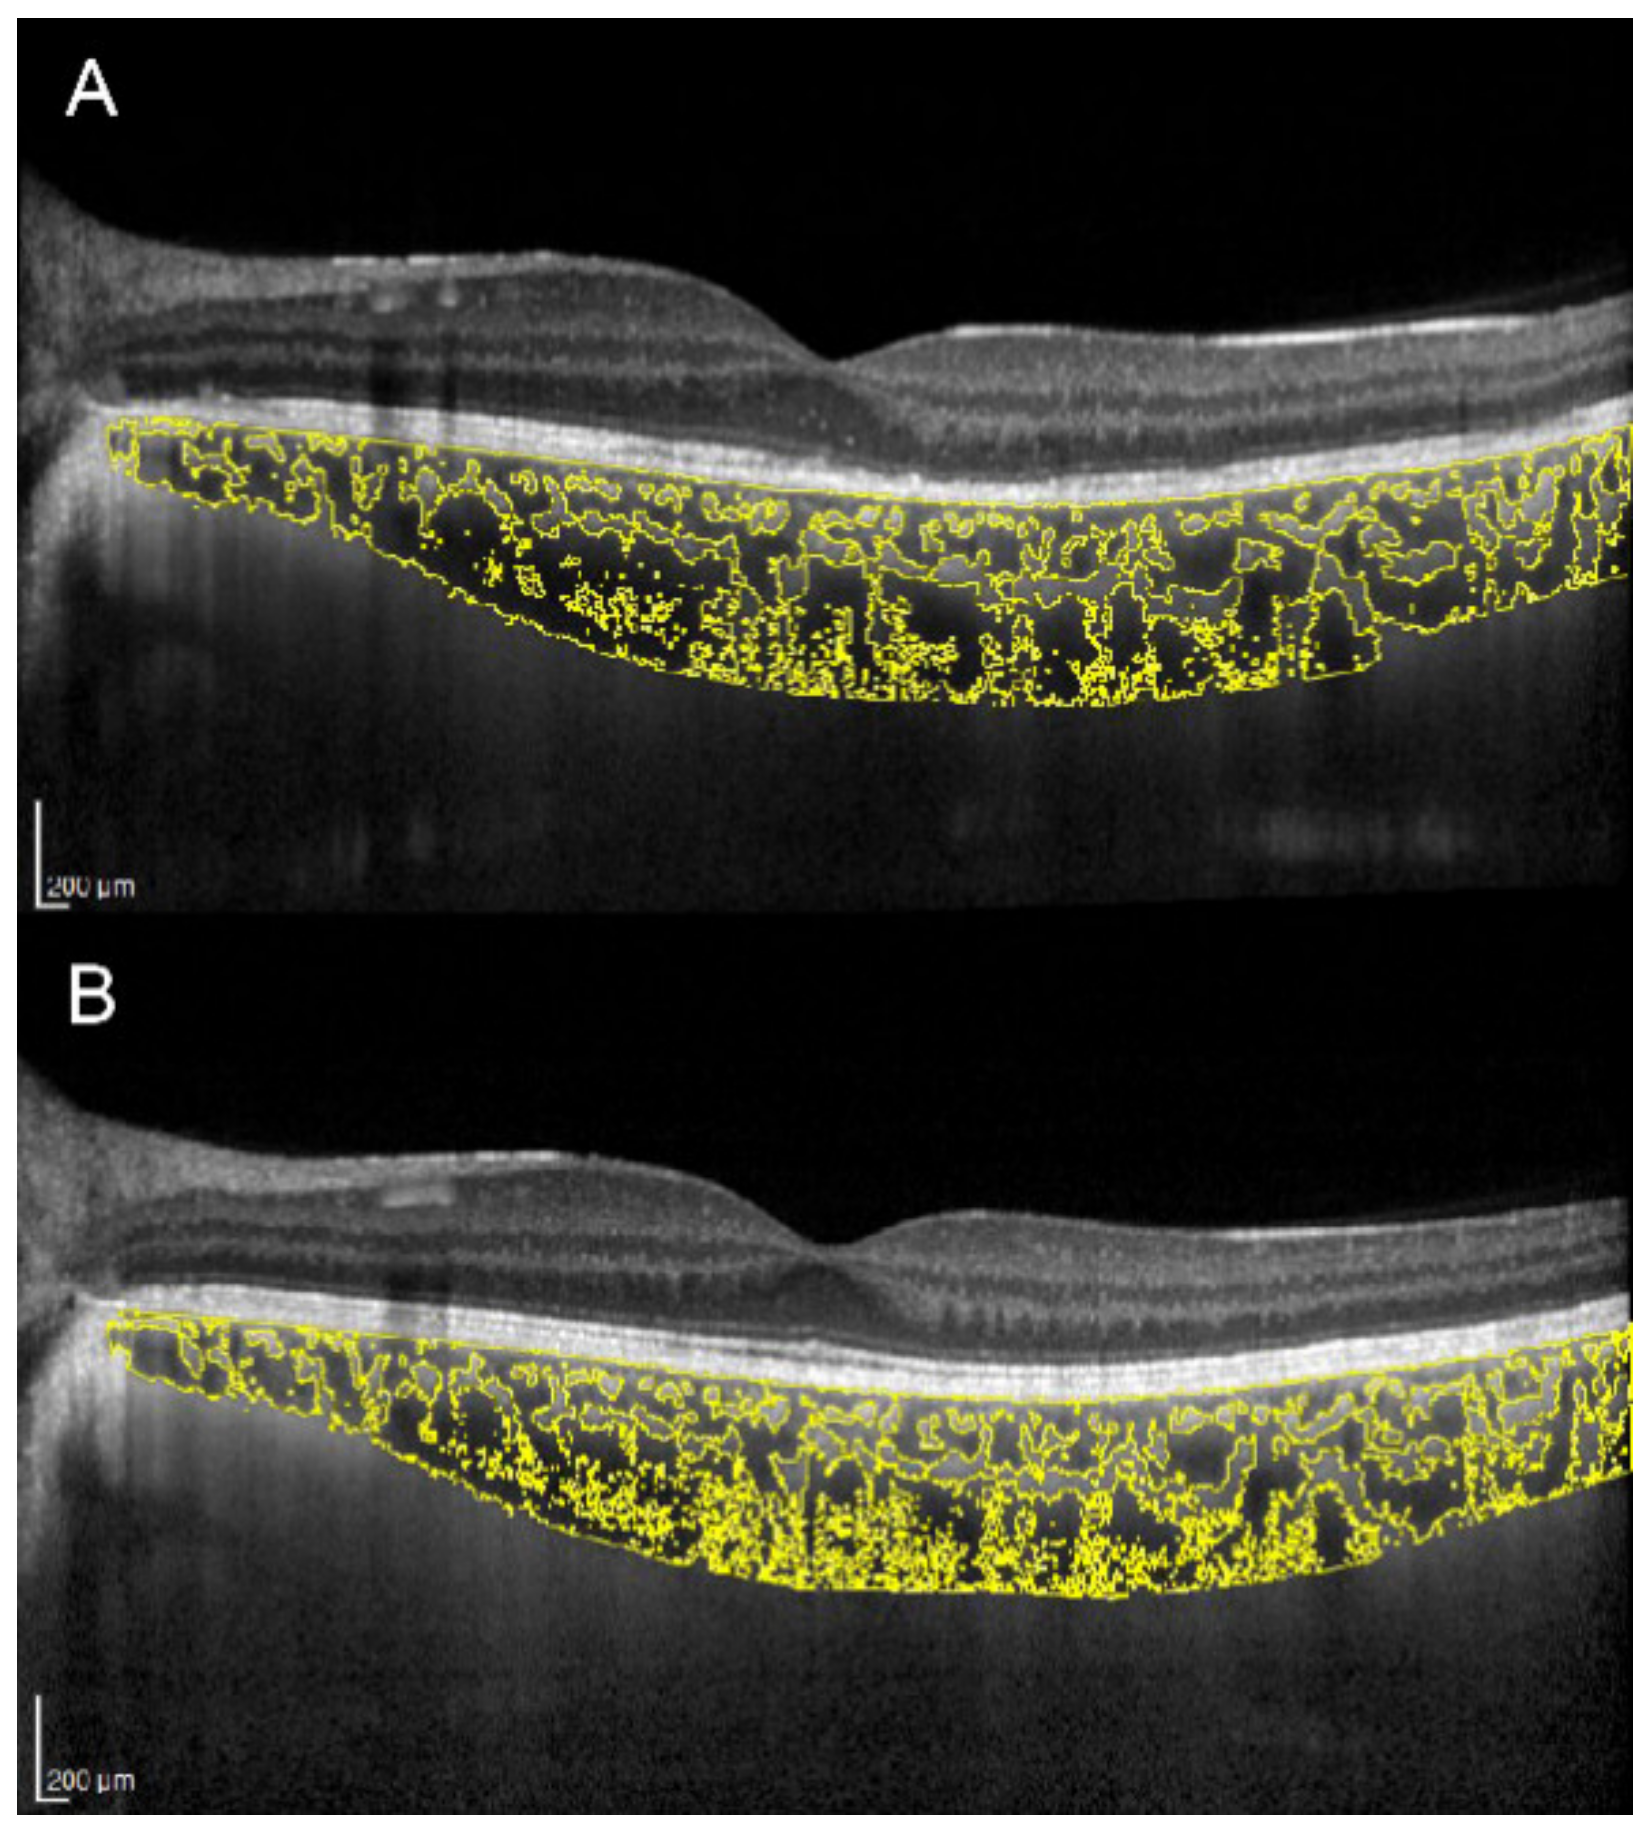

There is an ongoing debate as to whether the primary site of inflammation in multiple evanescent white dot syndrome (MEWDS) is the outer retina or the choriocapillaris. Increased CT and CVI were demonstrated in the acute stage of MEWDS, with subsequent reversal of choroidal changes along with outer retinal restoration and visual function recovery (Figure 2) [28]. This suggests an inflammatory involvement not only of the choriocapillaris, but also of medium and large choroidal vessels.

Figure 2.

Choroidal vascularity index evaluation in a patient with multiple evanescent white dot syndrome. (A) In the acute stage, OCT shows ellipsoid zone disruption and a CVI of 69.3%. (B) In the healed stage, OCT shows normalization of the ellipsoid zone and a CVI decreased to 67.3%.

Nevertheless, it is still unclear if these choroidal changes play an active role in RPE/photoreceptor damage or are just a secondary effect of the inflammatory process occurring in the outer retina.